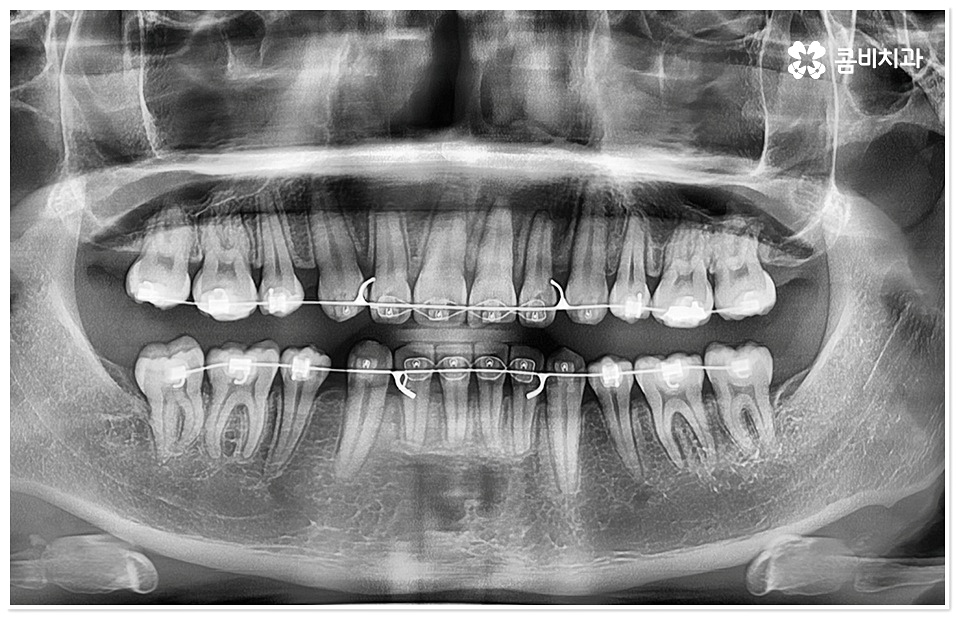

교정 치료란 특수한 장치를 이용해 치아를 원하는 방향으로 이동시켜 치아 배열과 교합을 올바르게 개선해 주는 과정으로 각자의 구강 구조가 다 다르기 때문에 정밀 검사를 통해 환자분들 각각의 치아 모양과 각도, 위치, 교합 뿐 아니라 잇몸 건강 상태 및 상악과 하악의 관계와 같은 구강 내 상황과 함께 입술, 전체 안모 등 대칭과 균형의 측면에서 모든 부분을 다각적이고 입체적으로 분석한 후 세밀한 맞춤 계획을 수립하는 것이 중요할 수 있는데요.

그러므로 3D CT와 같은 정밀 검진 장비와 3D 모르페우스와 같은 시스템을 갖추고 다양한 경험과 노하우를 바탕으로 정확한 진단 및 섬세한 플랜을 세울 수 있는 치과를 잘 알아보고 덧니치아교정 치료를 진행하실 필요가 있어요.